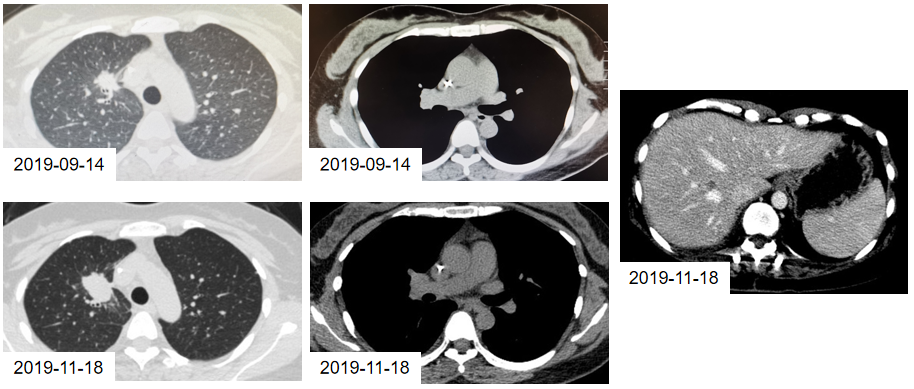

2019年11月18日,复查影像学结果提示:肺部原发病灶较前增大,肝脏出现新发病灶。

图3. 9月14日与11月18日的CT检查结果

2020年8月31日,CT检查提示:肺部病灶、肝脏病灶均较前明显增大,考虑奥希替尼耐药,无进展生存期(PFS)为9.1个月。

图5. 2020年4月14日与8月31日的CT检查结果